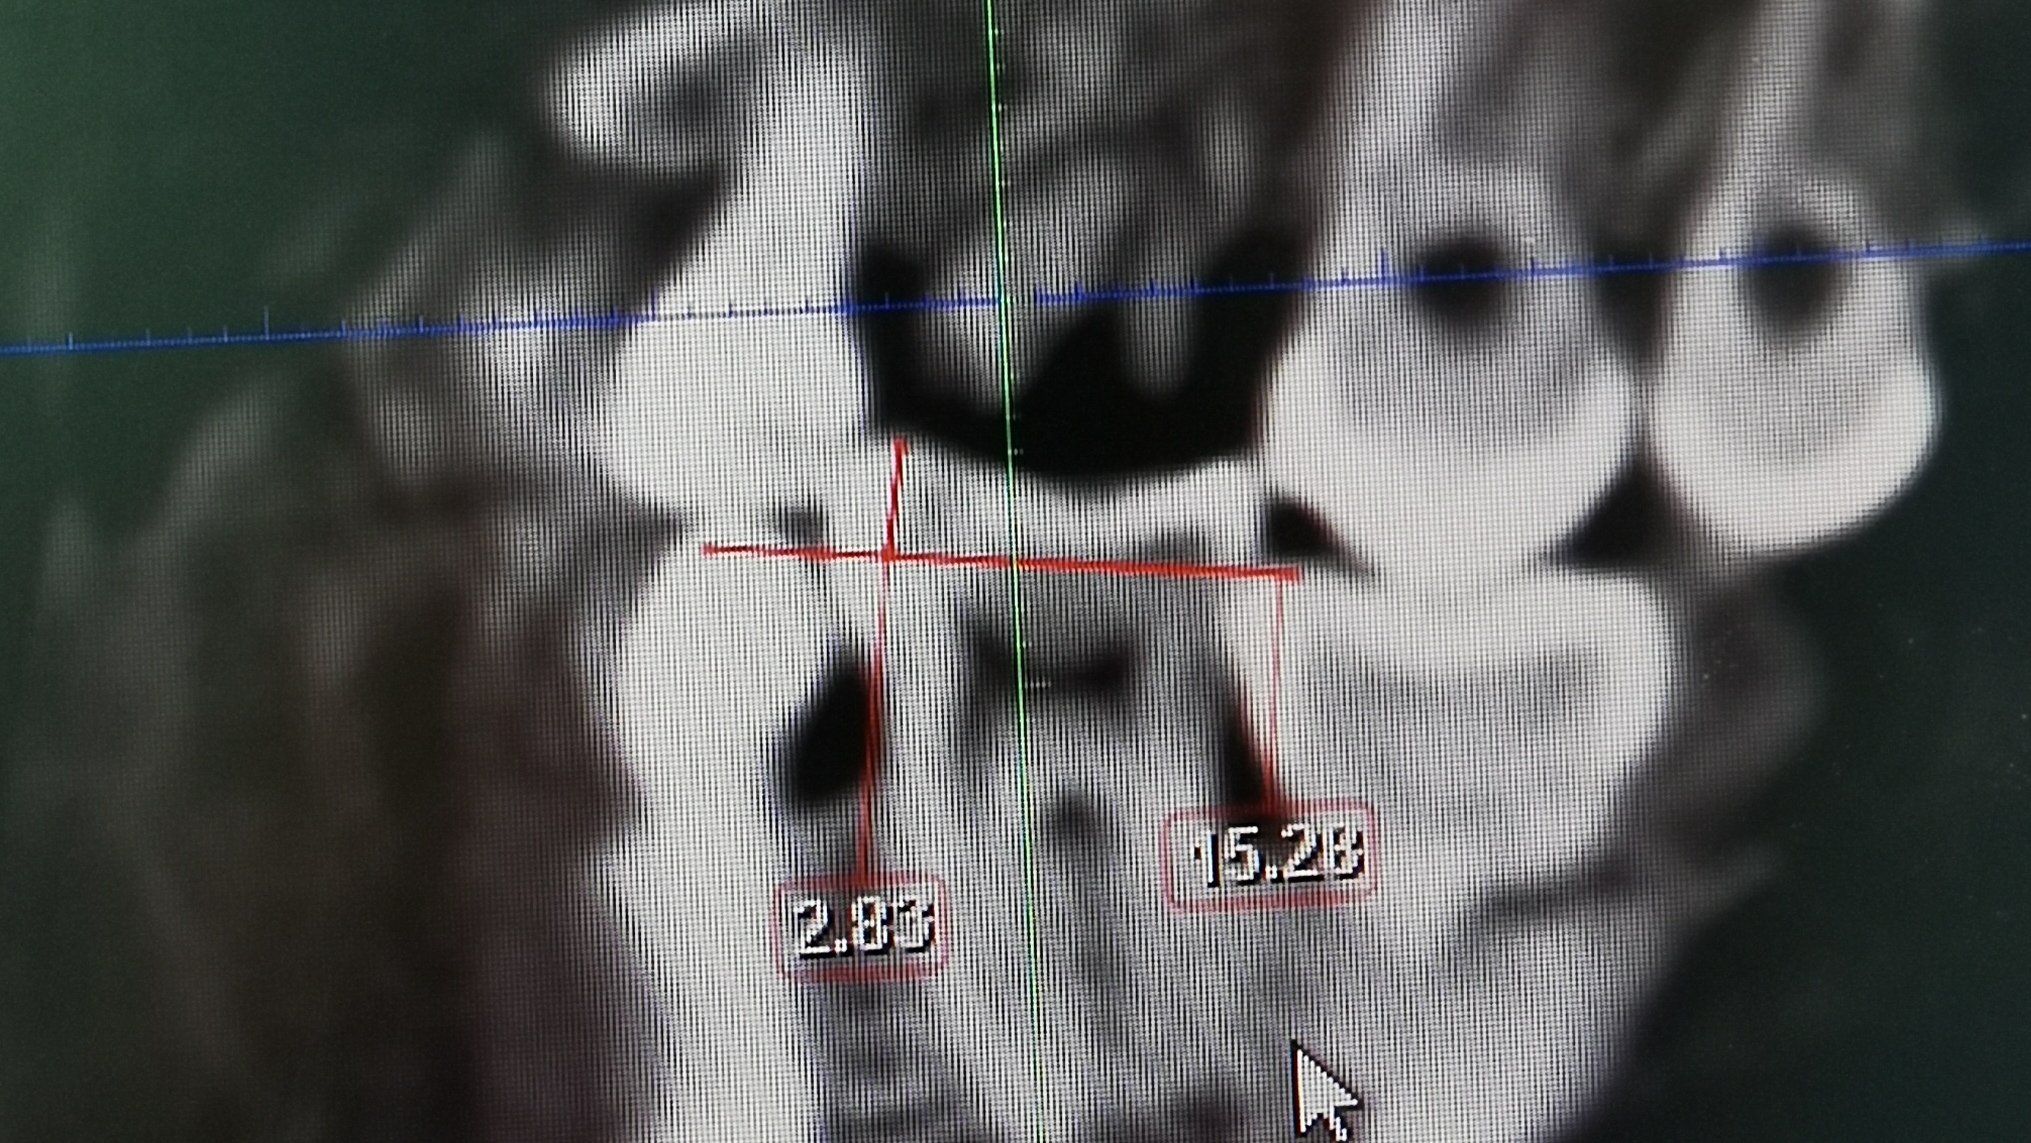

3、阻生智齿

长智齿的时候前面牙会受到压力邻牙或门牙有会被顶歪的可能